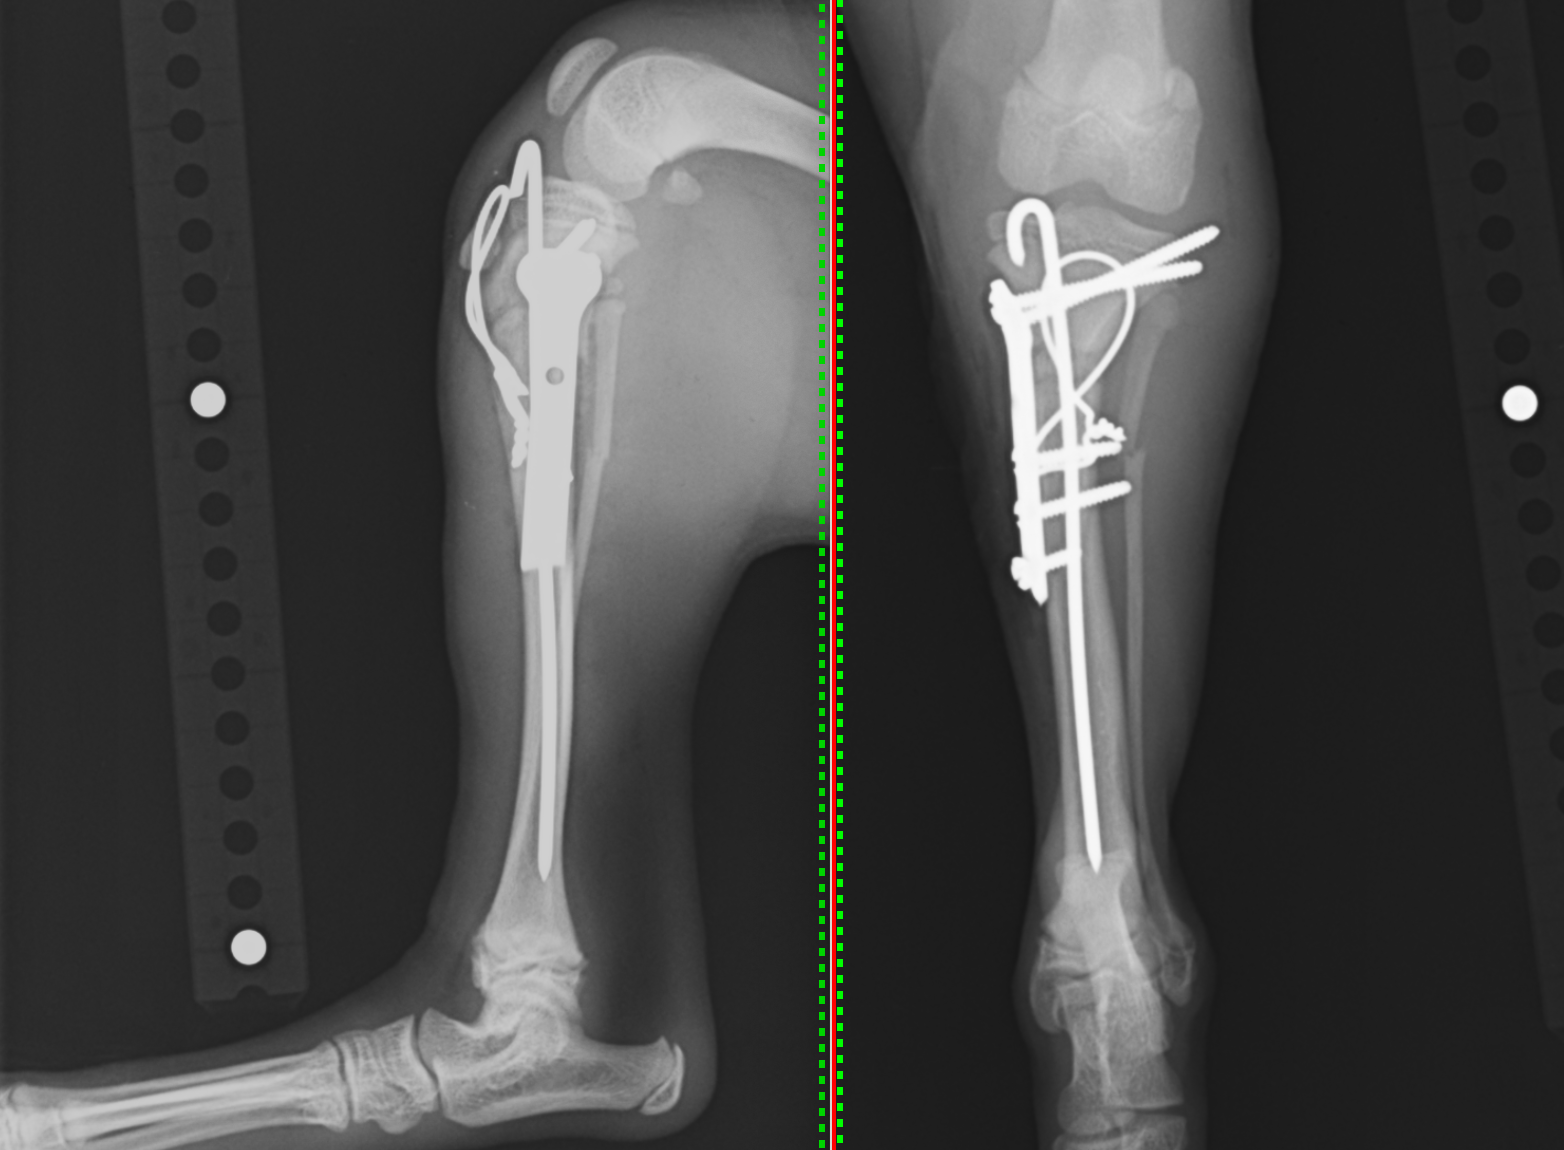

手術では髄内ピンというピンを用いて、折れ曲がりの方向に強度をもたせます。髄内ピンだけですと骨の回転が抑えられないので(ピンを軸に回る動きが出てしまう)、回転抑制のプレートを設置します。この方法を専門用語でプレートロッド法といいます。さらに、脛骨近位は膝蓋骨が付着しており、大腿四頭筋という後肢で最も強い筋肉が上に牽引する力が強く働きます。そのため、プレートを入れても後屈してくる事が多いので、それを予防するためにテンションバンドワイヤーを設置します。

右上に飛び出ているのが髄内ピン、真ん中のT字型のがプレートです。

最終的にテンションバンドワイヤーという針金のようなものをくくりつけて終了です。

術後のレントゲンです。骨折面もきれいに合っているのが分かります。

2ヶ月後には完全に骨癒合したためプレートとスクリュー・ワイヤーの抜去を行いました。